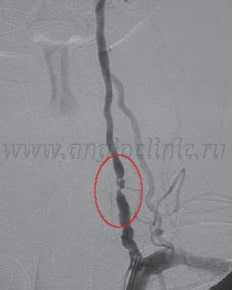

"Золотым стандартом" для диагностики стеноза позвоночной артерии остается цифровая рентгеновская ангиография , хотя она и несет определенные риски осложнений и требует опытного специалиста для соблюдения технологии обследования. В нашей клинике ангиография позвоночной артерии проводится после принятия решения о эндоваскулярном вмешательстве (стентировании) с целью окончательной диагностики. Непосредственно во время исследования возможно проведение операции.